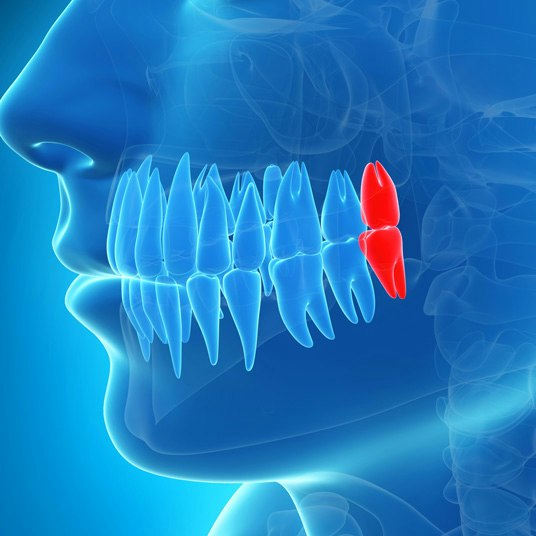

Root canal treatment is often the best solution to save a damaged or infected tooth. But how do you know if you might need one? While only a dentist can confirm if a root canal is necessary, certain symptoms are key indicators. Here are some signs you should never ignore:

5. Cracked or Chipped Tooth

A crack or chip in your tooth can expose the pulp to bacteria, leading to infection. Even if there’s no immediate pain, a damaged tooth increases the likelihood of needing a root canal.